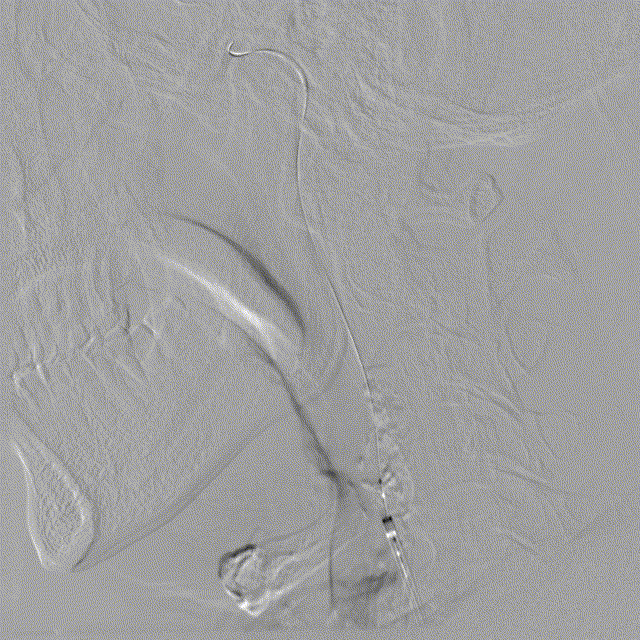

右侧颈动脉系统造影显示:右侧颈内动脉起始段及颅内段未见狭窄;大脑中动脉显影可,远端血流速度可;大脑前动脉显影浅淡,前交通动脉未开放,右侧胚胎大脑后动脉。

左侧颈动脉系统造影显示:颈内动脉开口无狭窄,供血入颅;眼动脉段可见重度狭窄,狭窄率约70%;同侧大脑中动脉及大脑前动脉未见狭窄,前交通动脉开放代偿右侧大脑前动脉供血,左侧后交通动脉未开放。

左侧锁骨下动脉造影显示:左侧锁骨下动脉、椎动脉开口及颅内段均未见异常,基底动脉及各分支显影可。

Simmons动脉导管同轴输送7F EasyRadial™输送导管至左侧颈内动脉起始段,随后撤出Simmons动脉导管及泥鳅导丝。

路图下,微导丝塑猪尾引导3.5*15mm 颅内球囊扩张导管送至颈内动脉眼动脉段狭窄处,微导丝置于M2段。

颅内球囊扩张导管进行球囊扩张。

球囊泄压后造影。

球囊扩张满意,撤出颅内球囊扩张导管。

输送3.5*15mm 药物涂层支架至眼动脉段。

颅内球囊扩张导管再次进行球囊扩张。

撤出球囊,释放支架。

术后造影示无明显残余狭窄,颅内血管无明显栓塞。